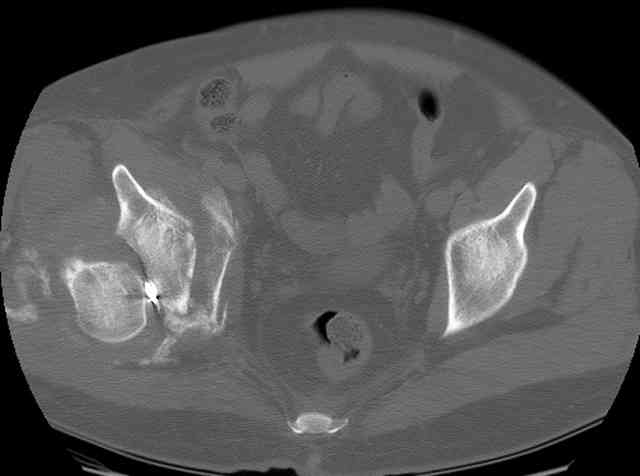

You can adjust the quadrilateral surface contact point as needed to get the fracture to reduce...we plan this based on the fracture orientation on the preop CT scan images...the clamp should be balanced to avoid over compressing one portion and distracting the other limb. Go back to and you¹ll see on the injury CT where the clamp tines need to be.

Here's a pic from the foot of the bed and you can see the clamp in the wound and the knee is extended so he must've had a tight rectus. The C-arm is rolled back to an obturator oblique image to reveal the anterior column...we put a slight outlet tilt to combine the images and give a better view of the anterior column...we can see the posterior column limb reduction in the wound, we can palpate the quadrilateral surface limb, and the image demonstrates the anterior column portion...you can adjust the tilt and rotation to image tangentially to the fracture plane if you'd like. We've inserted a 2mm K wire to site the starting point and aim/orientation for the drill and screw

Prone Imaging

same image, just another look.